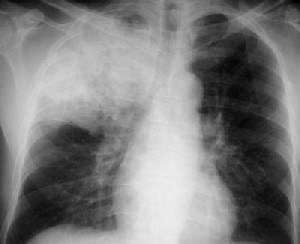

Назначается рентгенография грудной клетки, бронхоскопия, КТ или МРТ легких и органов грудной полости. Иногда проводится кардиограмма, а при подозрении на компрессию опухолью — исследование соответствующего органа.